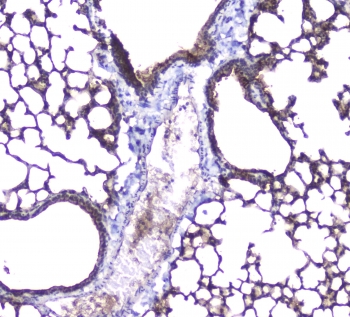

IHC staining of FFPE rat lung with AQP5 antibody at 1ug/ml. HIER: boil tissue sections in pH6, 10mM citrate buffer, for 10-20 min followed by cooling at RT for 20 min.